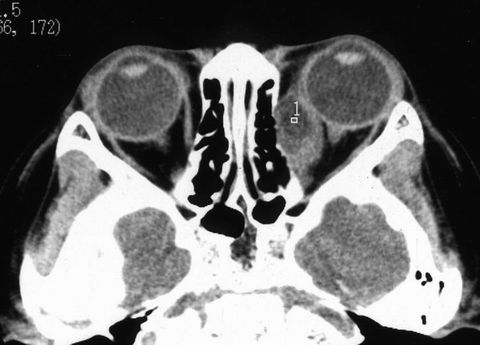

左眼球渐进性突出,间断红肿2年。曾用抗生素+激素治疗有效。但反复发作,眼球突出加重。于2000年5月住院治疗。入院检查:全身正常。眼科检查:双眼视力1.0。左眼眼睑无红肿,眼球突出测量:右眼12㎜,左眼18㎜,眶距95㎜。眶压增高,眼球突出,轻度外移位,内收明显受限,外展仅30°(图1)。眼底后极部轻度水肿。CT扫描如图2。入院期间左眼突然红肿,眼球突出加重,眶压增高,轻度恶心(图3)。

3.如何分析CT片 左球后内侧椭圆形占位病变  内密度低(表示有液体)有时可在低密度的病变内显示点状高密度(囊虫)。邻近副鼻窦正常